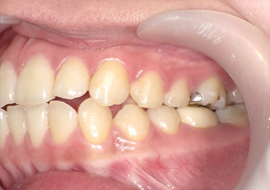

症例3

Before

After

| 主訴 | 上下の歯のガタガタを治したい |

|---|---|

| 年齢 | --- |

| 治療 期間 |

約10ヶ月 |

| 治療 内容 |

インビザラインiGoで上下顎の治療。 狭まっていた歯並びを広げることで、 ガタガタに並んでいた歯を綺麗に並べた。 |

| 治療費 | ¥517,000(税込)+月額調整料 |

| 治療のリスク | 歯と歯の間を削ることでスペースを確保するので、 場合によっては歯が染みる症状が出ることがある。 |